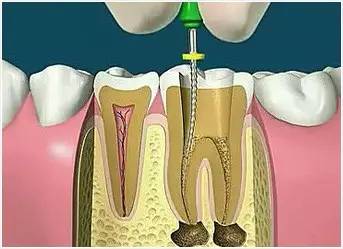

3、確定根管工作長度

應(yīng)用平行投照X線方法、根管長度測量儀確定根管度,最好插針拍X片。

4、根管預(yù)備

根管清理成形的目的是去凈根管壁上的感染物,通過根管器械的切削作用去除感染的牙本質(zhì)并清理根管壁細(xì)菌以利于根管充填。

5、根管沖洗、消毒

根管沖洗的目的是清除微生物、沖掉殘渣,潤滑根管器械和溶解有機殘渣。然后,再進(jìn)行根管消毒,使根管內(nèi)達(dá)到無菌狀態(tài)。